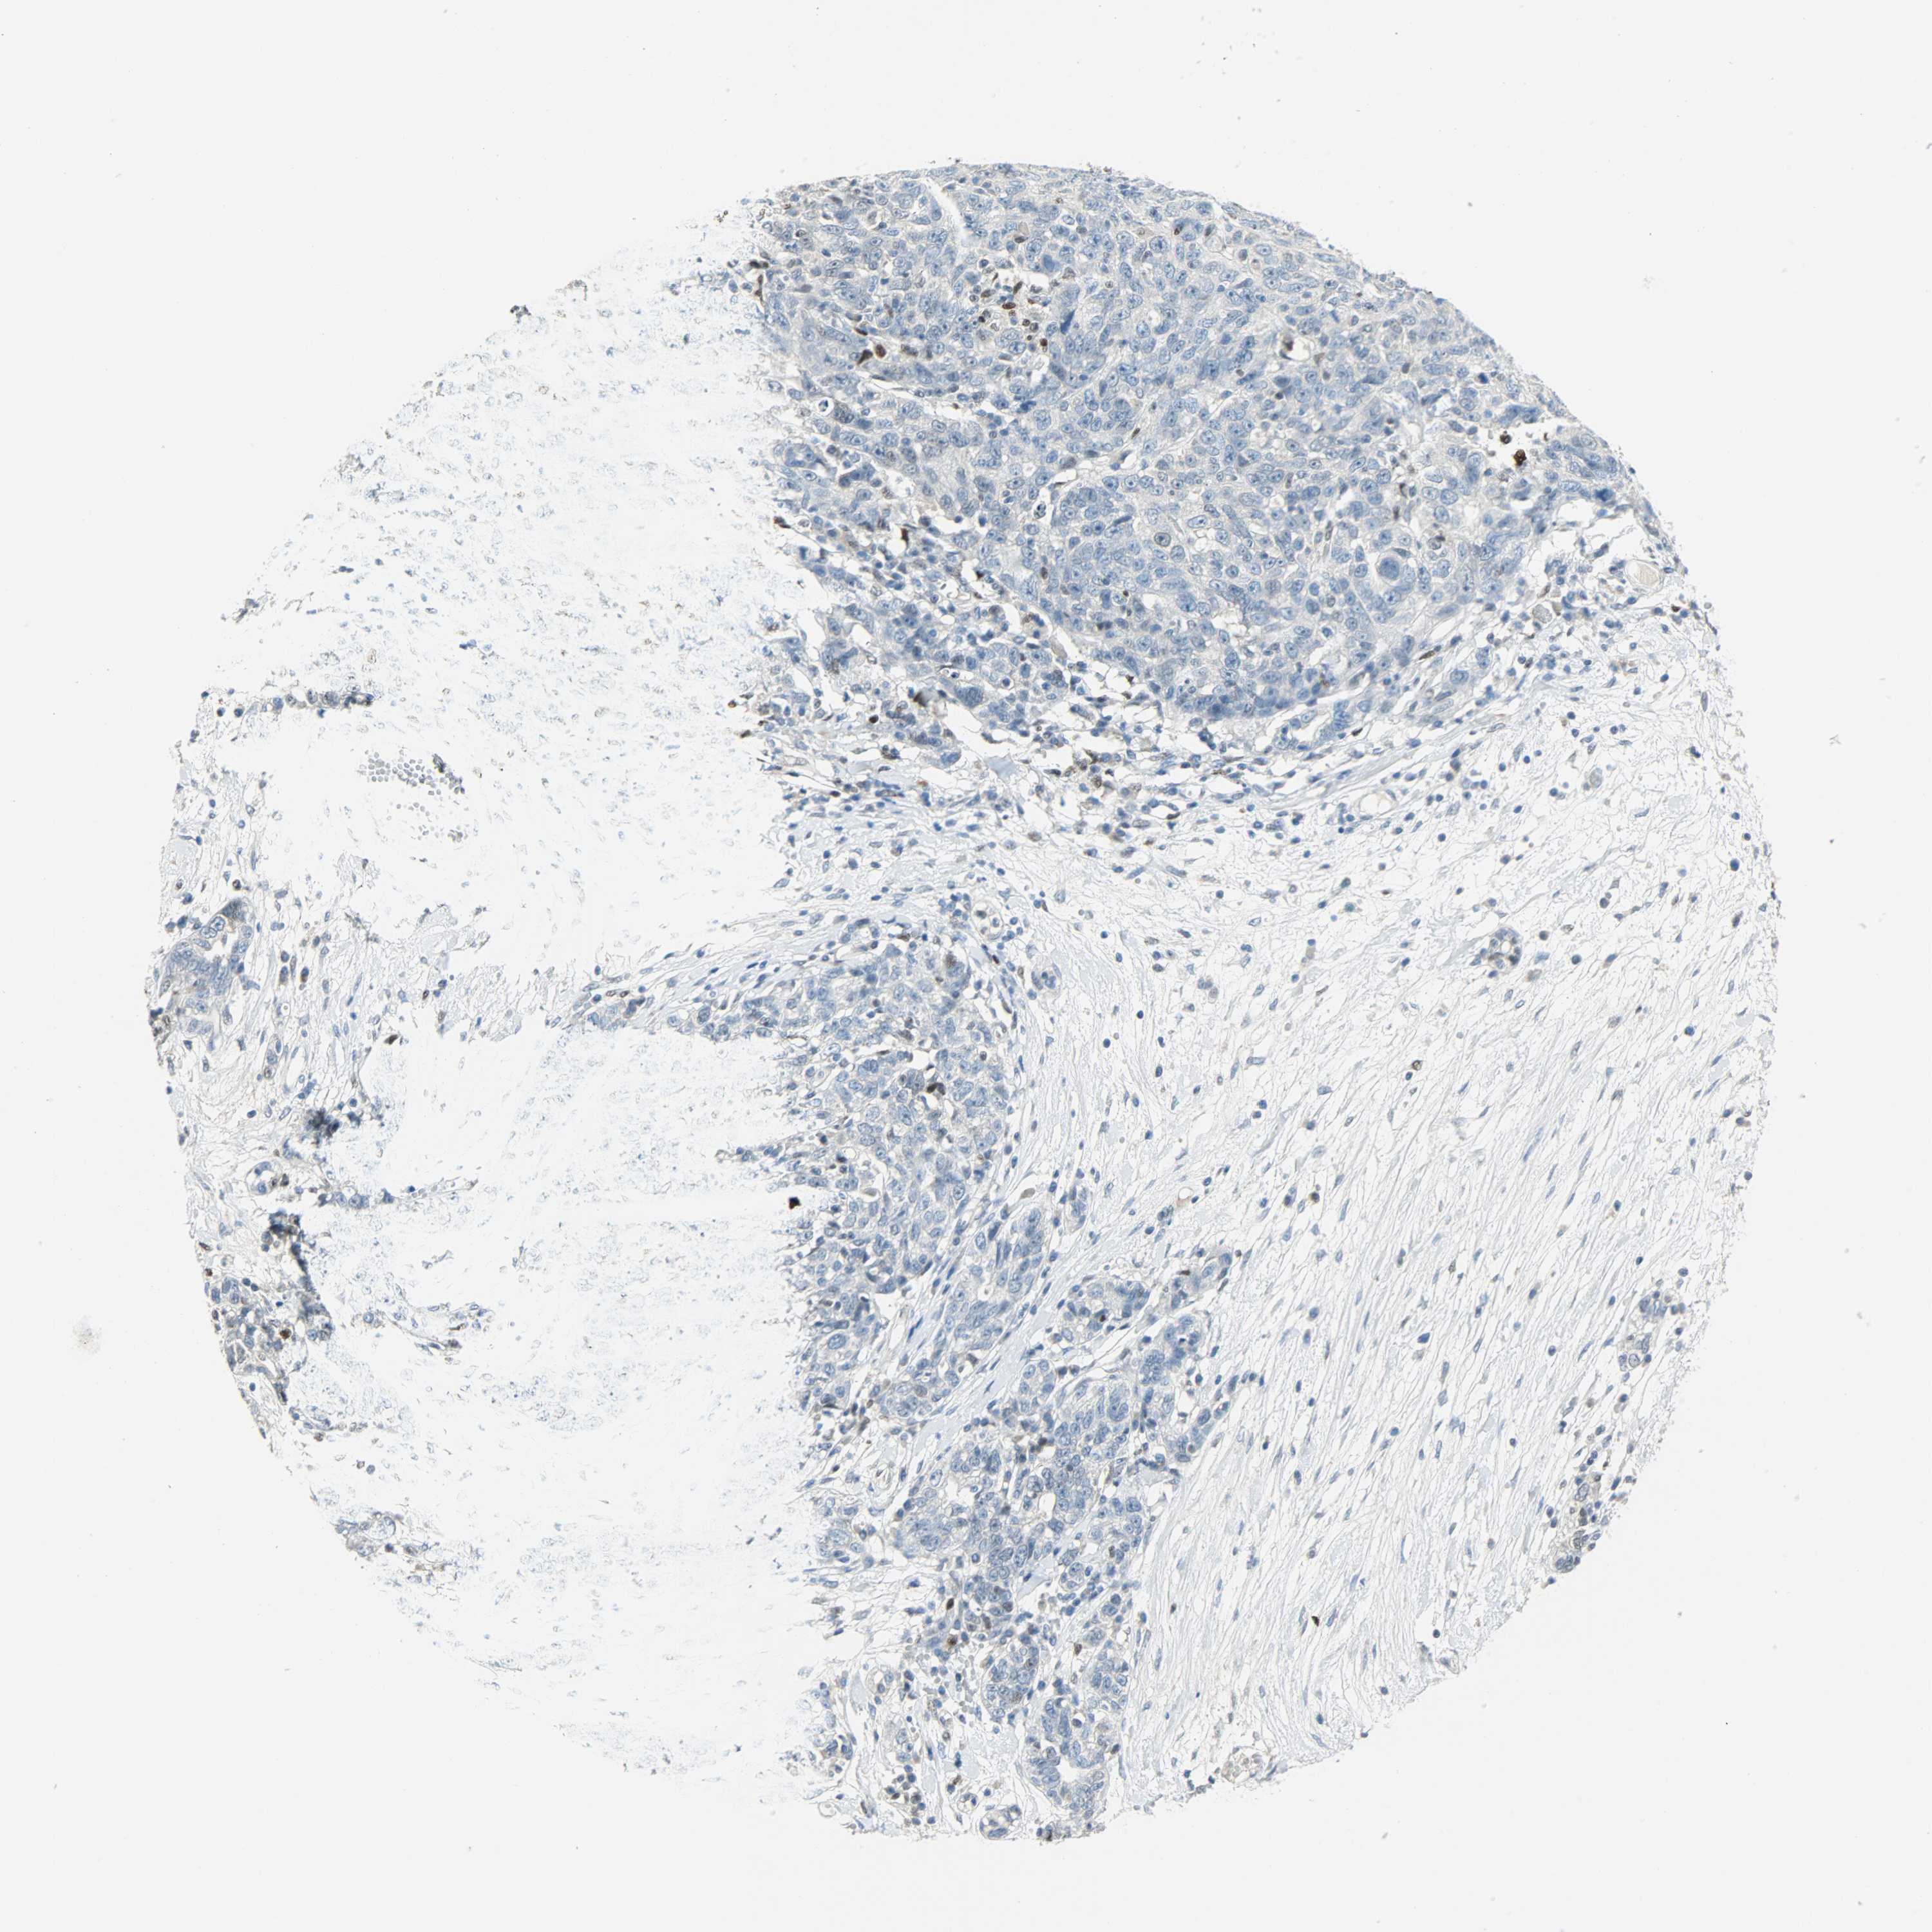

OVARIAN CANCER - Protein expressioni

A mouse-over function shows sample information and annotation data. Click on an image to view it in a full screen mode. Samples can be filtered based on level of antibody staining by selecting one or several of the following categories: high, medium, low and not detected. The assay and annotation is described here.

Note that samples used for immunohistochemistry by the Human Protein Atlas do not correspond to samples in the TCGA dataset.

Antibody stainingi

Antibody staining in the annotated cell types in the current human tissue is reported as not detected, low, medium, or high, based on conventional immunohistochemistry profiling in selected tissues. This score is based on the combination of the staining intensity and fraction of stained cells.

Each image is clickable and will lead to virtual microscopy that enables deeper exploration of all samples and also displays staining intensity scores, fraction scores and subcellular localization as well as patient and tissue information for each sample.

Antibody HPA019149

Antibody CAB004464

Staining

High

Medium

Low

Not detected

Intensity

Strong

Moderate

Weak

Negative

Quantity

>75%

75%-25%

<25%

None

Location

Nuclear

Cytoplasmic/membranous

Cytoplasmic/membranous,nuclear

Cystadenocarcinoma, serous, NOS

Carcinoma, endometroid

Cystadenocarcinoma, mucinous, NOS

Carcinoma, NOS